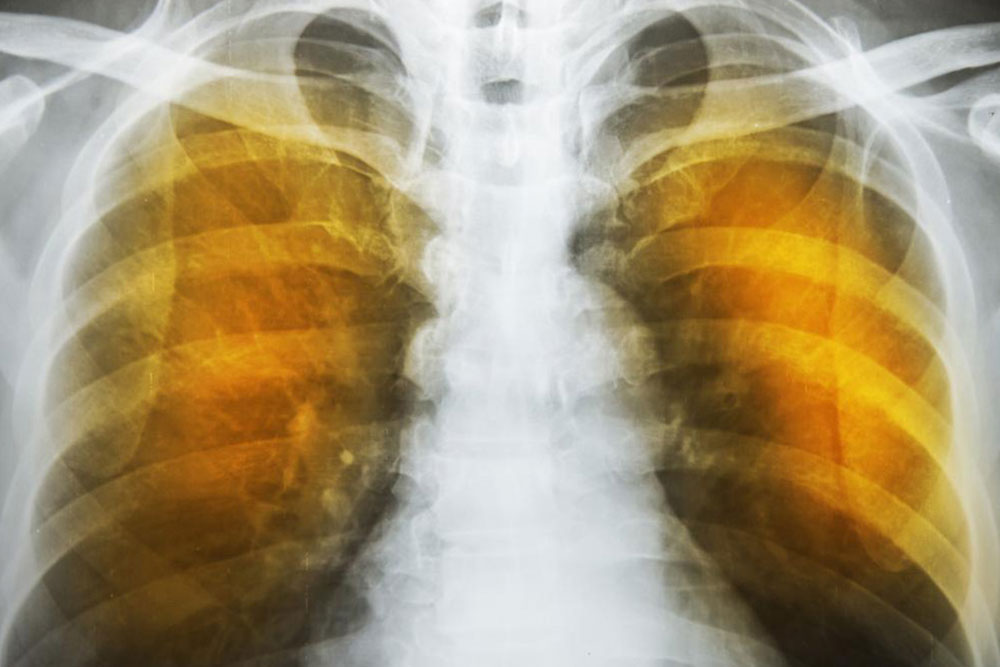

Emphysema is an oppressive respiratory disorder which results from the disintegration of the alveoli, i.e., the tissues where the interchange of gas with blood takes place. Destruction in any large scale will reduce the gas transfer area and the process of gas transfer itself, leading to oxygen starvation or hypoxia. When conventional treatment with bronchodilators, corticosteroids etc. have ceased to give relief, one has to resort to a method known as Long Term Oxygen Therapy or LTOT.

Another complication is the alveoli becoming weaker, and then starting to break. When this assumes larger scale, vacant spaces are formed called bullae. This reduces the gas transfer area as well as the capacity of the lung to expand. These are often have to be surgically removed to allow more space for the lung to expand. In the ultimate case, lung transplant becomes the only choice. Another scenario is a large-scale disintegration of alveoli that can cause pneumothorax, which is a condition in which the chest cavity is filled with air and the lungs collapse. This is a very serious condition if not fatal.